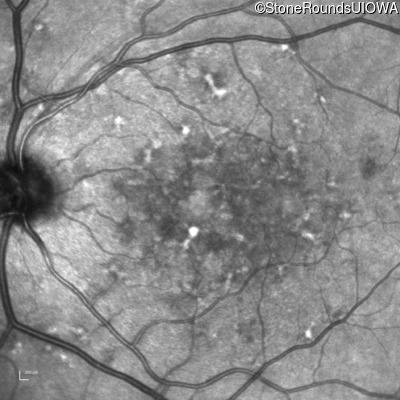

AR Stargardt Disease (IIA)

Age at visit: 59 years (Visit 3)

This 59 year old woman first noticed vision loss in her right eye a few months earlier. She has a cousin with Rhodopsin-associated RP.

Diagnosis & molecular findings

Disease Gene Allele 1 variant(s) Allele 2 variant(s) Inheritance mode

AR Stargardt Disease ABCA4 Arg219Thr AGA>ACA Gly863Ala (G)GA>(G)CA AR